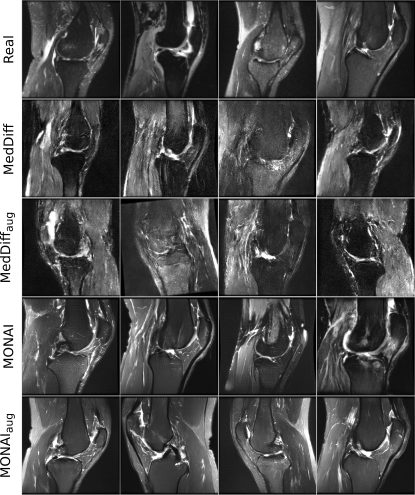

Figure 5: Representative cross sections of real (Real) and copies (MedDiff, MONAI) detected in the MRNet datasets. Copies show a high resemblance to the corresponding real samples.

Refer to caption

In MRNet dataset, (40.2, 48.2) % of the training data were memorized in (MedDiff, MONAI), and (76.1, 87.4) % of the synthetically generated samples were identified as patient data copies in (MedDiff, MONAI). Fig. 5 shows copies that were detected in both MedDiff and MONAI along with the closest training samples. In the MRNet dataset, which contained full 3D volumes, most of the global structure was preserved, albeit with notable differences in fine structural details between MedDiff and MONAI. MedDiff-synthesized images were noisy and unable to capture low-level structural details (Supp. Fig. S1). MONAI-synthesized images, on the other hand, had a lower noise level but were slightly blurry (Supp. Fig. S1). In MRNet, while both networks produced patient data copies, both models were unable to generate small structural details.